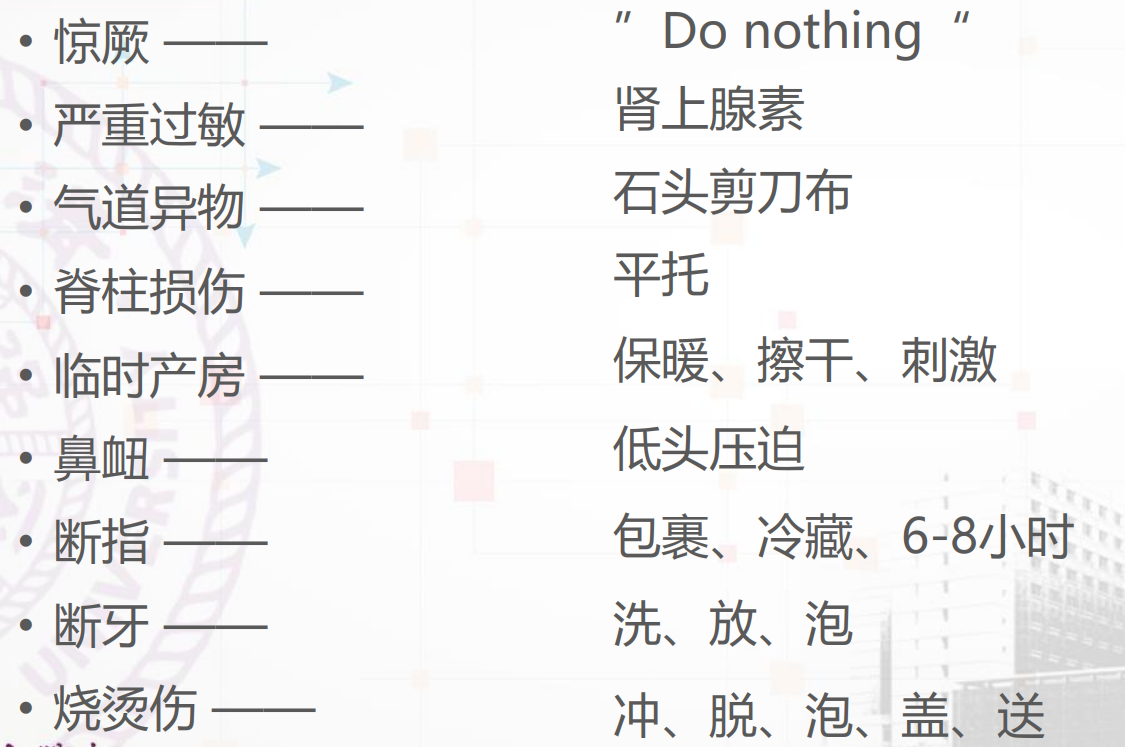

5. 争分夺秒——成人及儿童常见急症的紧急处理

海姆立克急救法:

可以参考链接:百度百科_海姆里克腹部冲击法

Heimlich⼿法虽卓有成效,但也可产⽣合并症。